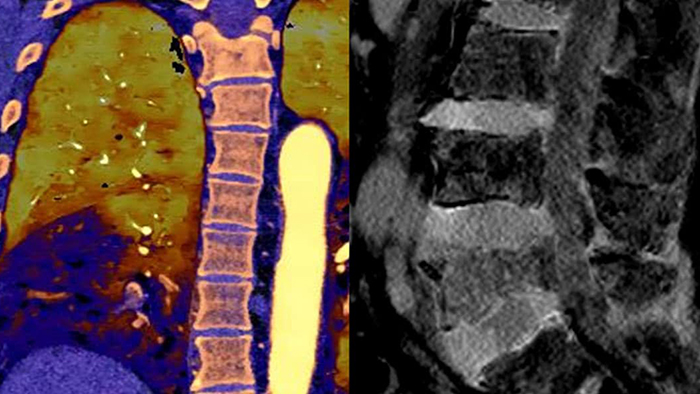

Spectral detector CT transformed conventional CT to a quantitative CT. The second-generation Philips Spectral CT 7500 receives an Aunt Minnie Award for Best New Radiology Device in 2021.

Unlike traditional CT images, spectral-detector CT images capture spectral information 100% of the time —without special planning or set-up. That means you can analyze the spectral data in any image retrospectively, using a variety of spectral viewing tools. You can, for example, adjust the monoenergetic level or get Zeffective maps.

Spectral detector simultaneously absorbs and differentiates high and low energy from a single polyenergetic X-ray beam. Spectral results are acquired within a single scan without the need for special modes.

Spectral CT helps me objectively differentiate contrast staining from hemorrhage, obviating the need for additional follow up scanning and prolonged patient observation, which can result in reduced costs and radiation exposure to patients.1,2